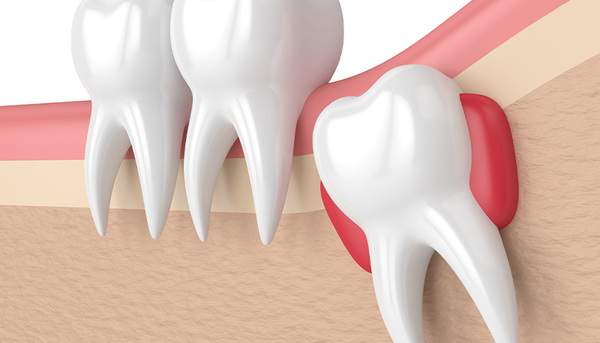

親知らずが歯ぐきに埋まっており抜歯が難しい場合のイメージ

親知らずの抜歯は難しいものとそうでないものがあります。見るべきポイントは、下記になります。

親知らずの生えている方向ですが、やはり真っ直ぐ生えているものは簡単に抜ける傾向にあります。

しかし、親知らずは一番最後にはえる歯なので、スペースがなく、斜めにはえる方がほとんどだと思われます。

その傾斜角度で難易度が変わってきます。

また、親知らずの位置が、骨に埋まっていればいるほど難易度は上がります。